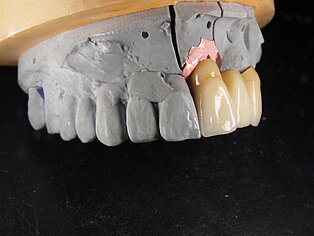

Meisterarbeit von Peter Dengel